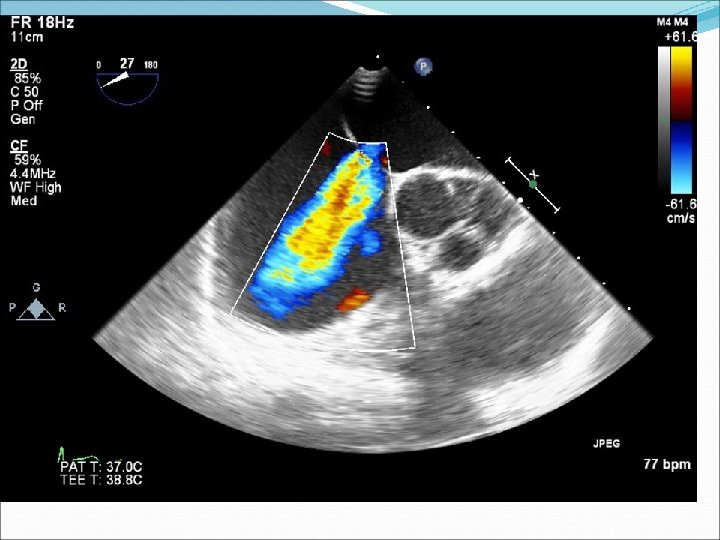

Defekt síňového septa: diagnostika echokardiografie, často jícnová: dilatovaná pravá komora zkratový proud barevným dopplerovským vyšetřením při přítomnosti trikuspidální regurgitace neinvazivně z rychlosti regurgitace odhadovat výši systolického tlaku v plicnici kalkulovat systémový průtok(Qs) ve výtokovém traktu levé komory a plicní průtok(Qp) v kmeni plicnice a počítat jejich poměr EKG: obraz bloku pravého raménka Tawarova u 95 % pacientů je projevem opožděné aktivace dilatované pravé komory Skiagram hrudníku : dilatace pravé komory, pravé síně, dilatace plicnice, zvýšenou plicní kresbu. Katetrizační vyšetření : před uzávěrem defektu u starších pacientů k posouzení plicní vaskulární rezistence a k provedení selektivní koronarografie.